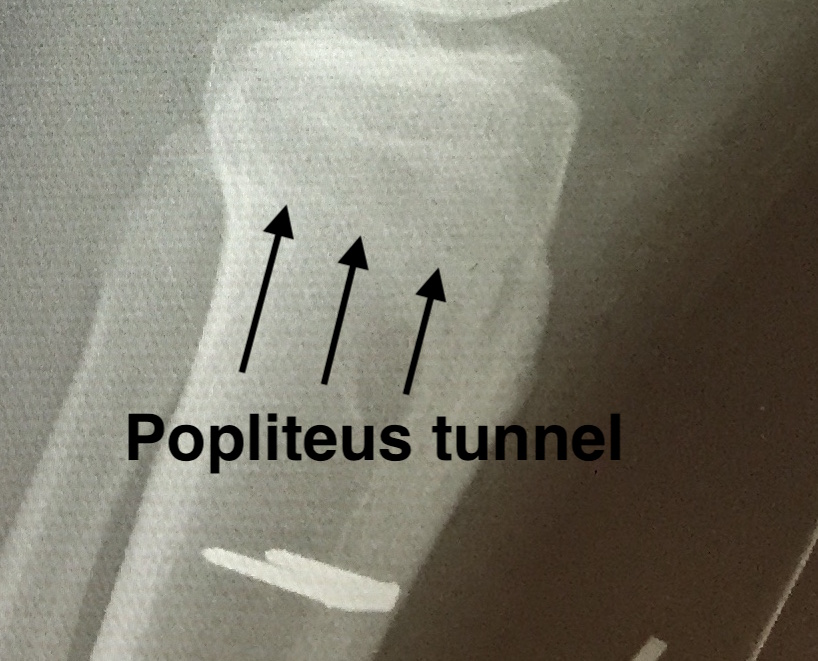

Popliteus tibial tunnel

- anterior entry point is distal and medial to gerdy's tubercle, below tibial plateau

- create posterior window

- anterior to lateral head of gastrocnemius, posterior to knee capsule, above LHB

- insert retractor under lateral head of gastrocnemius to protect vascular structures

- identify and ligate the lateral inferior geniculate artery

- identify with a finger the proximal tibio-fibular joint

- the posterior tunnel must exit medial to this joint, below tibial plateau

- at approximate site of the popliteus musculotendinous junction

- pass beath pin anterior to posterior

- drill to 9 mm

Popliteus tunnel 1Popliteus tunnel 2